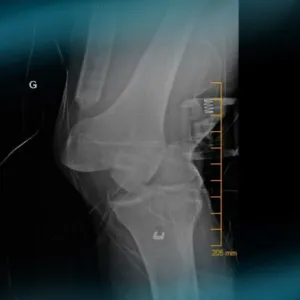

A professional rugby player who underwent ACL reconstruction with fascia lata (Mc FL) a few years ago, presents with knee torsional trauma.

After looking at the X-ray, MRI and pre-op testing, what can you say about this multiligament knee injury? What's the best course of action and how would you approach this case?